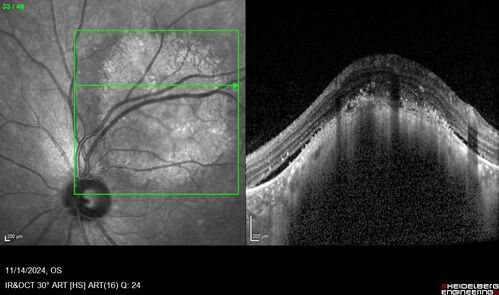

Small choroidal melanoma

28 year old man Serial images suggested that the lesion is growing

OD: sc20/16

OS: sc20/40+2

IOP: TP: OD:19 OS:16